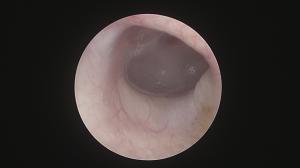

先日、半年の経過確認で来院されました

調子も良く安定しています!

処置後の最初には注意が必要ですが、ひとまず安心です。

このまま再発せずに経過することを期待しつつ、今後も定期的に確認していきます。